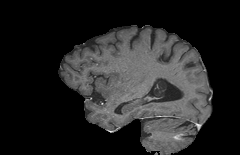

To compute the subtraction images 𝐳{LD,SD}subscript𝐳LDSD\mathbf{z}_{\{\mathrm{LD},\mathrm{SD}\}}bold_z start_POSTSUBSCRIPT { roman_LD , roman_SD } end_POSTSUBSCRIPT from a pre-contrast 𝐱PCsubscript𝐱PC\mathbf{x}_{\mathrm{PC}}bold_x start_POSTSUBSCRIPT roman_PC end_POSTSUBSCRIPT and CE 𝐱{LD,SD}subscript𝐱LDSD\mathbf{x}_{\{\mathrm{LD},\mathrm{SD}\}}bold_x start_POSTSUBSCRIPT { roman_LD , roman_SD } end_POSTSUBSCRIPT image pair, we perform the preprocessing pipeline illustrated in Figure 2. First, the brain region 𝐛{0,1}n𝐛superscript01𝑛\mathbf{b}\in\{0,1\}^{n}bold_b ∈ { 0 , 1 } start_POSTSUPERSCRIPT italic_n end_POSTSUPERSCRIPT is extracted by an affine registration of an atlas brain towards the pre-contrast image 𝐱PCsubscript𝐱PC\mathbf{x}_{\mathrm{PC}}bold_x start_POSTSUBSCRIPT roman_PC end_POSTSUBSCRIPT to minimize the effects of motion artifacts from facial regions in the subsequent steps. Second, the itk-elastix library is used to co-register the low-dose 𝐱LDsubscript𝐱LD\mathbf{x}_{\mathrm{LD}}bold_x start_POSTSUBSCRIPT roman_LD end_POSTSUBSCRIPT or standard-dose 𝐱SDsubscript𝐱SD\mathbf{x}_{\mathrm{SD}}bold_x start_POSTSUBSCRIPT roman_SD end_POSTSUBSCRIPT images to the corresponding pre-contrast images. Third, each scan is coarsely normalized by mapping its 95%percent9595\%95 % intensity percentile of the brain region to 1111. This coarse alignment of the intensity values is refined by a radiometric registration step computing a scalar to minimize a robust distance as performed in [9].

Refer to caption

Figure 2: Illustration of the preprocessing steps for extracting the initial low-dose subtraction image 𝐳~LDsubscript~𝐳LD\tilde{\mathbf{z}}_{\mathrm{LD}}over~ start_ARG bold_z end_ARG start_POSTSUBSCRIPT roman_LD end_POSTSUBSCRIPT from the pre-contrast 𝐱PCsubscript𝐱PC\mathbf{x}_{\mathrm{PC}}bold_x start_POSTSUBSCRIPT roman_PC end_POSTSUBSCRIPT and low-dose 𝐱LDsubscript𝐱LD\mathbf{x}_{\mathrm{LD}}bold_x start_POSTSUBSCRIPT roman_LD end_POSTSUBSCRIPT image. The top images in the steps show the transformed low-dose image while the bottom images visualize the effects on the subtraction image.